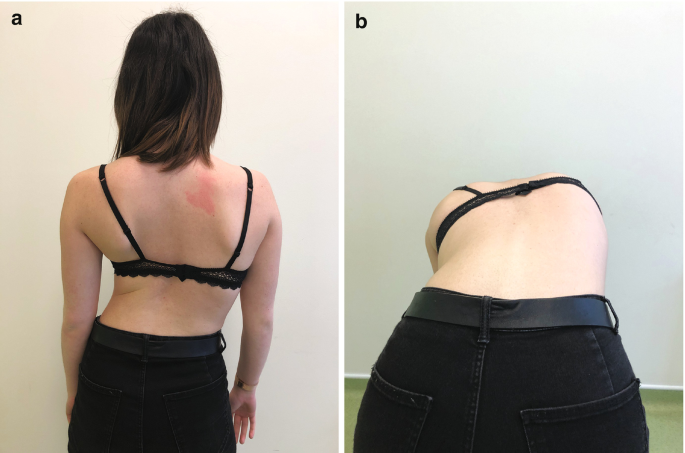

هذه التمارين تُحسن حركة المفصل وتمنع الشد العضلي الذي يؤدي إلى ميل الحوض.استخدام حزام اعوجاج العمود الفقري:

في بعض الحالات، ينصح الطبيب باستخدام أو حزام اعوجاج العمود الفقري للحفاظ على استقامة العمود الفقري أثناء فترة العلاج.

أحدث التقنيات العالمية: نعتمد على تقنيات حديثة مثل أجهزة التقييم الدقيقة وأحزمة التقويم المتقدمة مثل PioBrace.